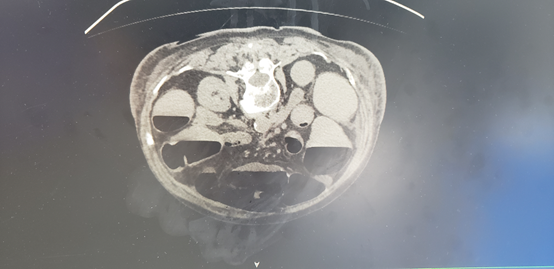

▲术后第三天复查CT

可见患者肠梗阻梗阻完全消失,支架完全打开